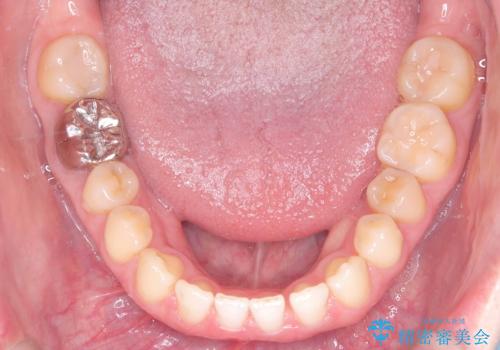

すきっ歯・切端咬合・空隙歯列|インビザラインで11ヵ月で治療完了

- すきっ歯と切端咬合(上下の前歯が先端で当たるかみ合わせ)を主訴にご来院された患者様です。

矯正検査を行った結果、非抜歯でインビザラインによる治療が可能と判断し、マウスピース矯正で改善を行いました。

11ヵ月で矯正治療が終了し、前歯の隙間も改善、見た目とかみ合わせも良好な状態となり、患者様にも大変ご満足いただけました。